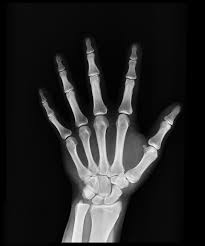

21 X-RAYS:

X-rays were accidentally discovered by Wilhelm Conrad Rontgen, a German Physicist in 1895 while he was experimenting with electric currents through cathode-ray tubes. He would eventually win the first Nobel Prize in Physics in 1901 for this important discovery. X-rays have changed the world since then. They are used for imaging, diagnosing and analyzing bones, teeth and other organs in the human body.

It is also used to check for bacterial infections such as tuberculosis. In surgery and tumor removal, X-rays are used to monitor the location of medical instruments. It is used in Airports for advanced security checks for scanning luggage. It has a lot of uses in industry. It is used to detect faults and cracks in metals, for checking material defects in building parts. It is used to check for the originality of valuable artwork and verify fossils and archaeological objects.